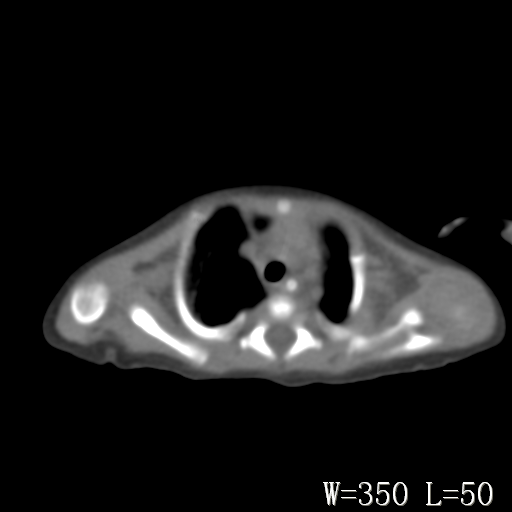

以下是引用改行者在2010-7-8 22:13:00的发言:[br]两肺野透光度降低伴细颗粒状影,两肺下叶见实变影,其内见支气管充气征。 多考虑新生儿肺透明膜病。